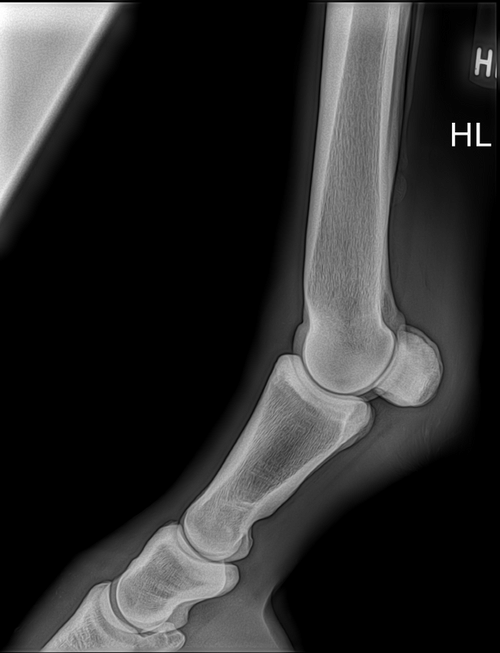

Röntgen des Fesselgelenkes

Röntgenuntersuchung